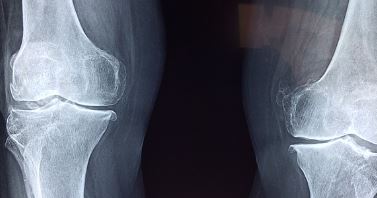

나도 며칠전 갑자기 무릎에 통증이 생겨서 정형외과에서 X-Ray 촬영도 하고, 한의원에서 침도 맞고 해서 간신히 상태가 좋아졌습니다.

1. 골관절염

골관절염은 무릎 관절에서 가장 흔하게 발생하는 형태의 관절염입니다.

관절을 보호하는 연골이 마모되면서 뼈와 뼈가 직접 마찰하게 되어 통증이 발생합니다. 주로 중년 이후에 발생하지만, 과체중이나 과거의 무릎 손상으로 인해 젊은 사람들에게도 나타날 수 있습니다.

초기에는 운동 후 또는 아침에 무릎이 뻣뻣하고 아픈 증상이 나타납니다. 치료 방법으로는 체중 감량, 물리치료, 약물 치료, 그리고 심한 경우에는 수술적 치료가 고려될 수 있습니다.

무릎통증이 발생하면 무엇보다 빠른 처치가 중요합니다. 괜찮아지겠지.. 하며 시간을 미루는 것보다는 정확한 원인을 찾아내어 그에 맞는 적절한 치료를 진행하면 빠른 시간내에 좋아질 수 있습니다.

그러니 조금이라도 아프면 우선 정형외과에 방문하여 엑스레이 라도 꼭 찍어보세요.